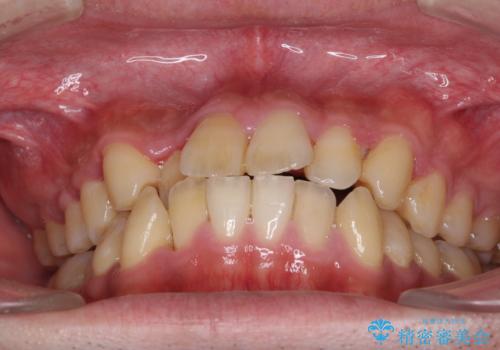

- 前歯のクロスバイトを気にして来院された患者様です。

デコボコやクロスバイトが散見されたため、IPR(歯と歯の間を削る)によってスペースを獲得できるように設計し、インビザラインにより治療を行うこととしました。